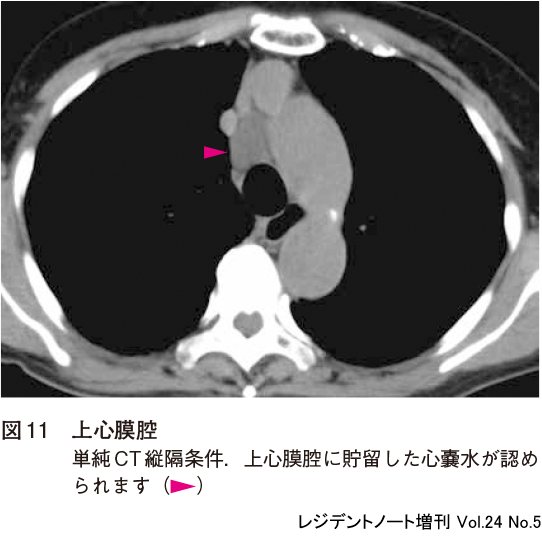

1)上心膜腔

心膜腔の広がりは個人差があり,上行大動脈の背側ではかなり頭側までみられることがあります(図11).上心膜腔(superior pericardial recess)に貯留した生理的な心嚢水はしばしば縦隔リンパ節腫大や縦隔腫瘍と間違えられます.特徴的な部位と,内部が水の吸収値であることに注意すれば正しく鑑別できるでしょう.